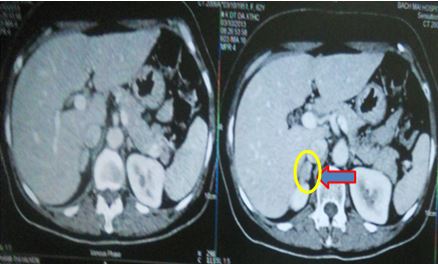

+ PET/CT :

Tại vị trí tuyến thượng thận phải có khối kích thước 3,3x3,0x4,7cm, tăng hấp thu F-18 FDG, max SUV = 15,3.

Hố chậu phải có khối kích thước 4,0x4,9x4,2cm, tăng hấp thu F-18 FDG, max SUV = 27,6.

Hình 1. Hình ảnh chụp PET/CT: Tuyến thượng thận phải có khối kích thước 3,3x3,0x4,7cm, tăng hấp thu F-18 FDG.

Hình 2. Hình ảnh chụp PET/CT: Hố chậu phải có khối kích thước 4,0x4,9x4,2cm, tăng hấp thu F-18 FDG